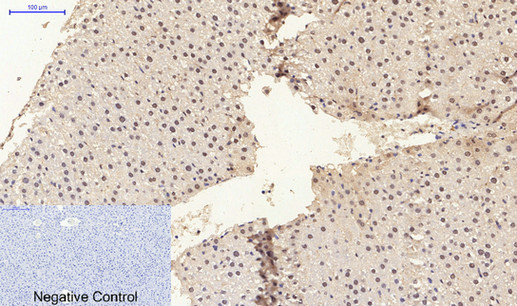

Immunohistochemistry analysis of paraffin-embedded rat liver tissue using ERβ antibody. High-pressure and temperature Sodium Citrate pH 6.0 was used for antigen retrieval.Negative control was used by secondary antibody only.